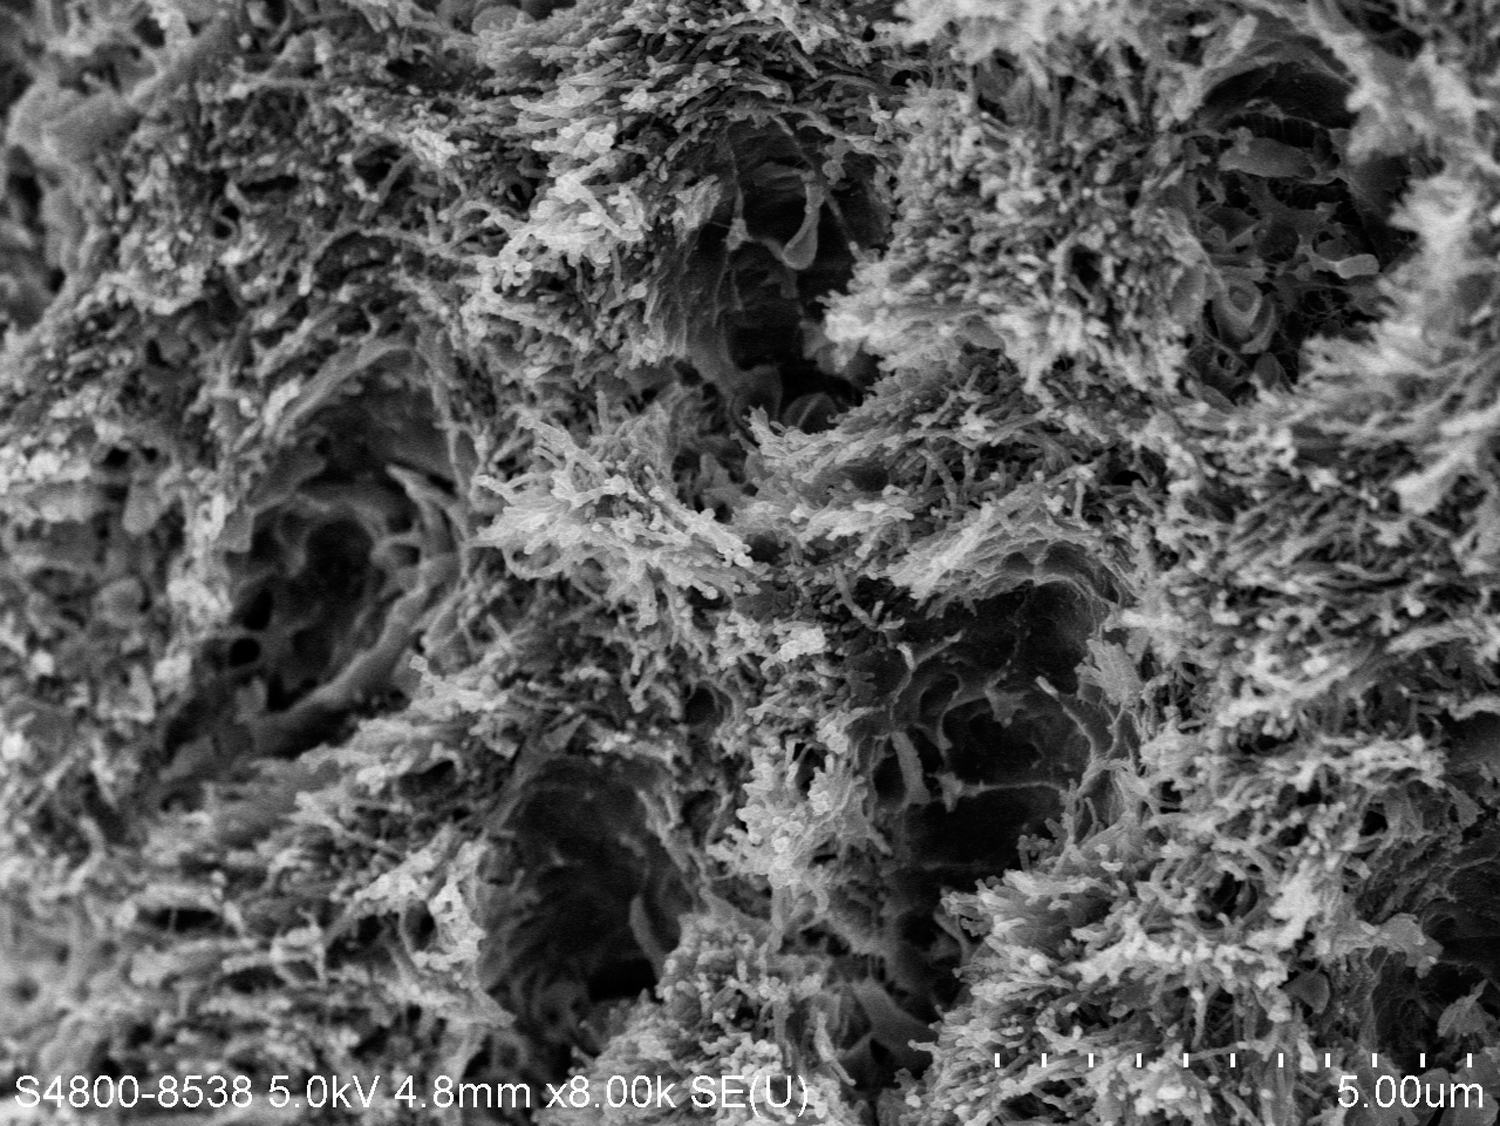

Fig 3. Scanning electron microscope (SEM) images of the dentin carious lesions. Fig 3: Surface morphology of arrested carious lesion. Fig 4: Surface morphology of active carious lesion. (images from Mei, et al, 201421 [reprinted with approval])

Fig 4. Scanning electron microscope (SEM) images of the dentin carious lesions. Fig 3: Surface morphology of arrested carious lesion. Fig 4: Surface morphology of active carious lesion. (images from Mei, et al, 201421 [reprinted with approval])